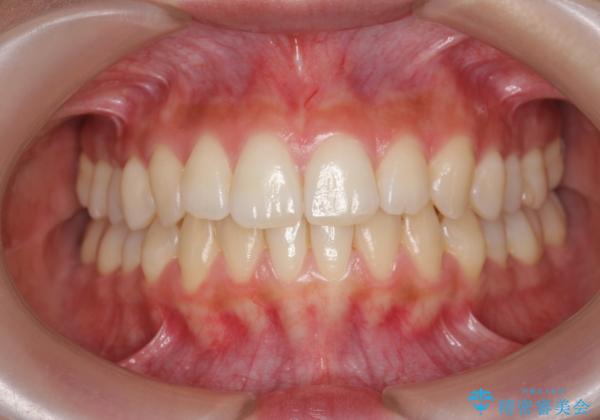

[ 前歯のねじれ・がたつき ] マウスピース矯正

- 前歯のねじれやがたつきを綺麗に並べたい、と矯正治療を希望され来院されました。

IPR(歯の間をすく)をくみこみ、がたつきを取り、かつ出っ歯にならないような矯正治療の計画をマウスピース矯正システムインビザラインで立てます。

気になっていたがたつき、ねじれが取れ、綺麗な歯並びに満足いただくことができました。